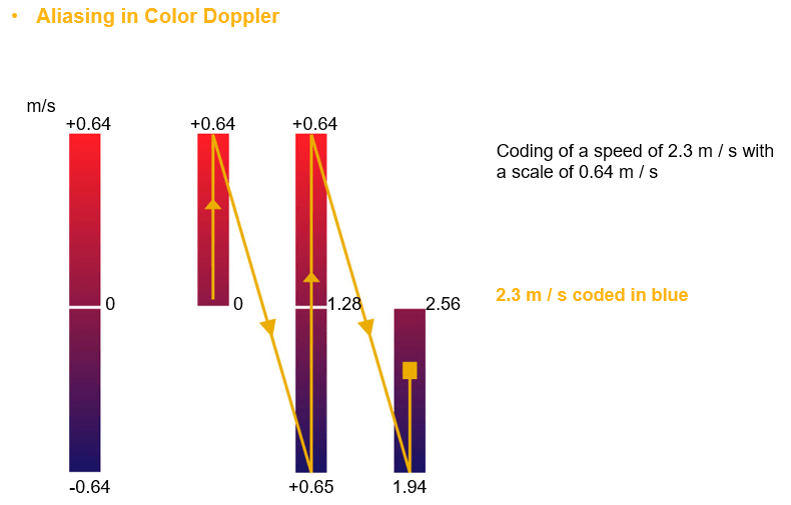

Aliasing occurs when the Doppler shift of the moving blood is higher than half of the pulse repetition frequency. Aliased signals are presented in the wrong direction (blue instead of red and vice versa). In this example the measured speed (2.3 m/s) is greater than half of the Nyquist limit (0.64 m/s), thus instead of being colored in red, it will be presented in blue as if the RCB is moving away from the transducer.